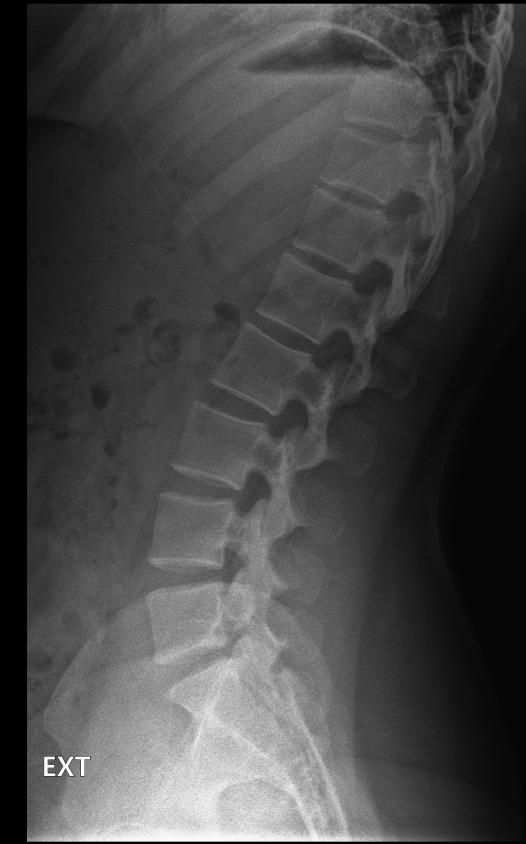

척추분리증인가요??(엑스레이 있어요)

한 병원에서는 척추분리증이라고 하고 한 병원에서는 척추분리증이 아니라고 해서요. 혹시 아래 사진에서 척추분리증 소견이 보이는 사진이 있나요??

여기까지가 a병원에서 찍은 사진이고 아래가 b병원에서 찍은 사진이에요!

• 1번 째 사진

• 2번 째 사진

척추분리증 맞습니다.

A병원 세번째 사진의 아래 부위에 척추분리증이 있는게 맞습니다.

B병원 사진에서는 비교적 흐리게 보이지만 잘 보면 B병원 엑스레이에서도 같은 부위에 분리증을 확인할 수 있습니다.